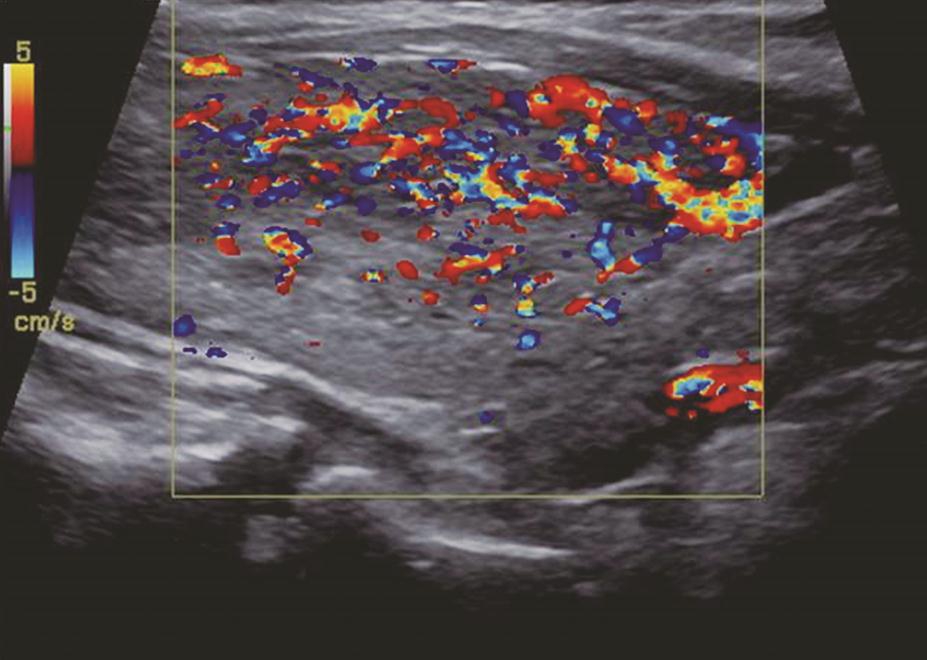

甲状腺呈弥漫性、对称性增大,包膜规则。腺体回声因病程和治疗情况而有所不同。未经治疗者,腺体回声均匀减低,少数呈散在、局灶性减低;病程长及反复发作者,腺体回声正常或稍强。腺体内可见多个管状无回声区(血管扩张)。彩色多普勒显示甲状腺内血流信号极为丰富,呈“火海征”(图3)。频谱多普勒可见甲状腺上、下动脉血流速加快,收缩期峰值流速多超过70cm/s(正常为30cm/s)(图4)。

图3右侧颈部纵切面:甲状腺右叶腺体血流信号丰富,呈“火海征”